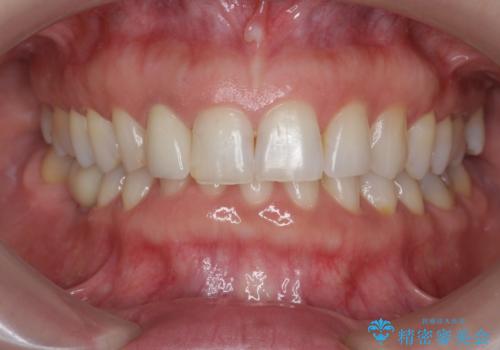

前歯の違和感 失活歯の根管治療とセラミック治療

- 16万円(仮歯・ファイバーコア・ジルコニアクラウンスペシャル)費用は治療当時の料金となります

セラミック治療を行う前にきっちりと根管治療を行うことが長期的に持つ可能性を高めます。